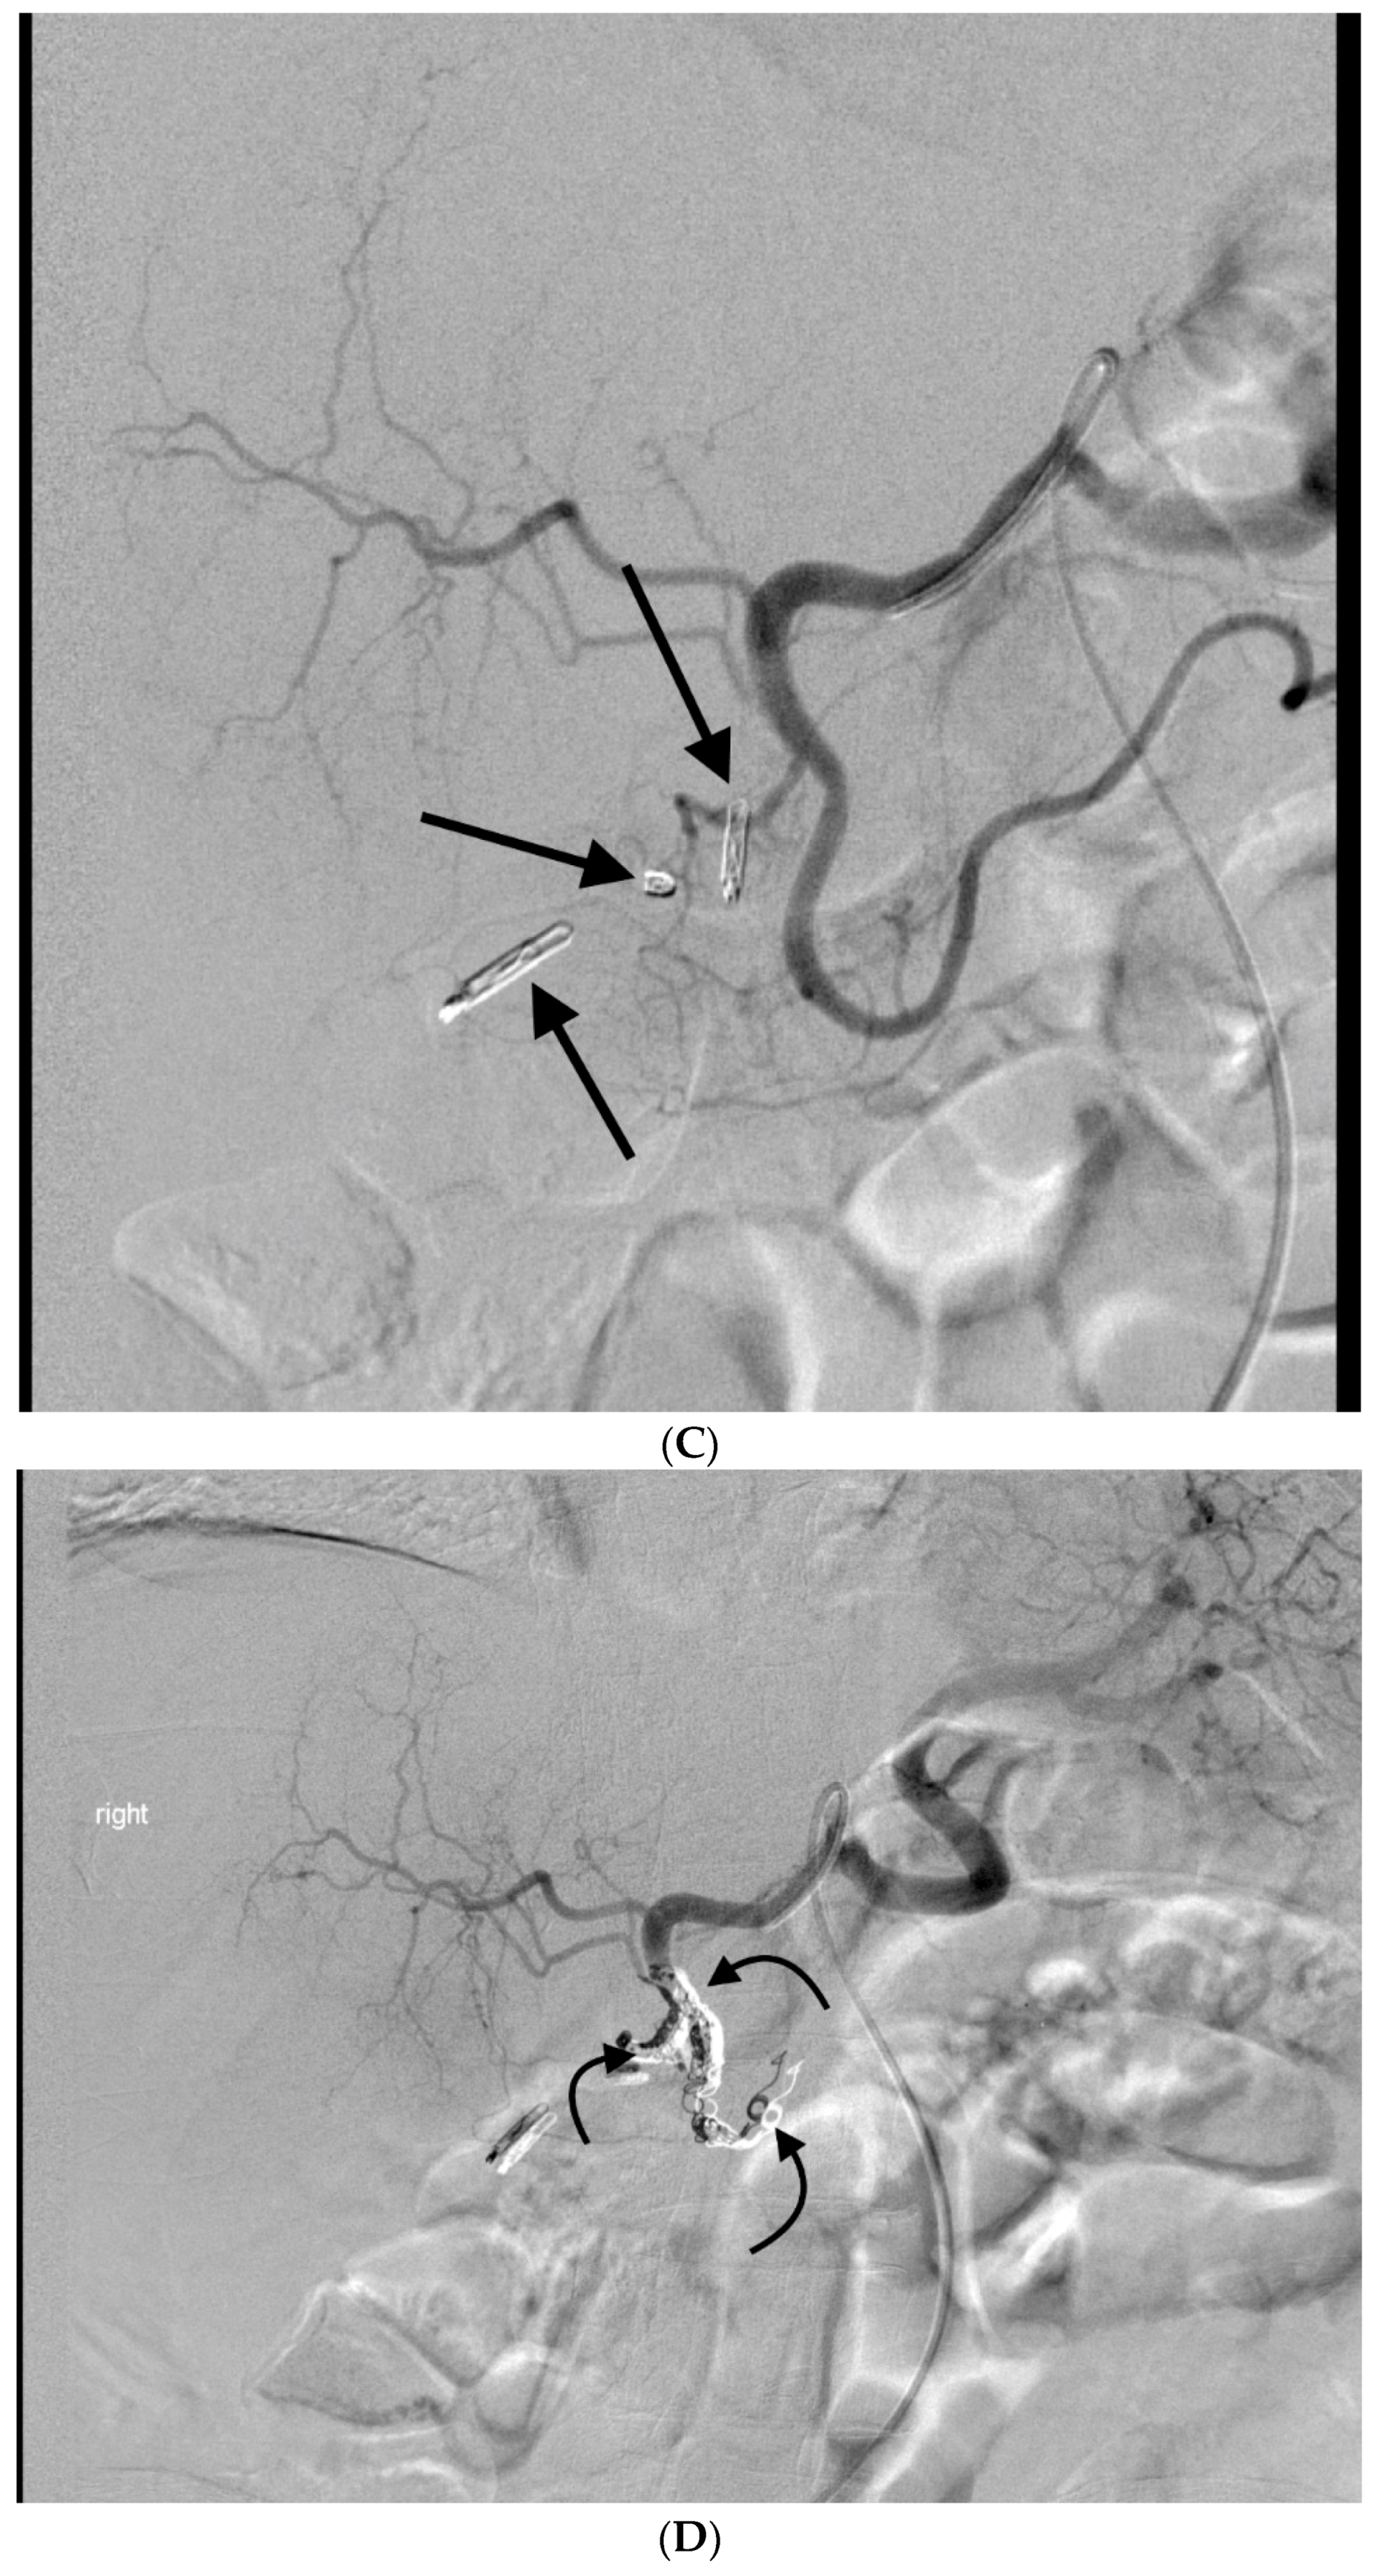

- Anil, G.; Tan, A.G.; Cheong, H.W.; Ng, K.S.; Teoh, W.C. Emergency gastroduodenal artery embolization by sandwich technique for angiographically obvious and oblivious, endotherapy failed bleeding duodenal ulcers. Clin. Radiol. 2012, 67, 468–475. [Google Scholar] [CrossRef] [PubMed]

- Enriquez, J.; Javadi, S.; Murthy, R.; Ensor, J., Jr.; Mahvash, A.; Abdelsalam, M.E.; Madoff, D.C.; Wallace, M.J.; Avritscher, R. Gastroduodenal artery recanalization after transcatheter fibered coil embolization for prevention of hepaticoenteric flow: Incidence and predisposing technical factors in 142 patients. Acta Radiol. 2013, 54, 790–794. [Google Scholar] [CrossRef] [PubMed]